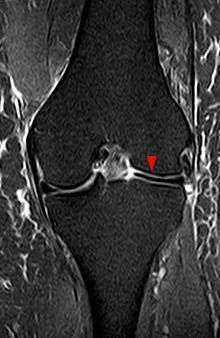

The transverse diameter of a normal meniscus is approximately 10 to 11 mm; therefore a normal meniscus body will be visible on only 2 slices of a MR with 4-5-mm sagittal slices. A discoid meniscus should be considered if more than two contiguous body segments are present. However, this method may lead to a false negative when evaluating people with the Wrisberg variant of discoid meniscus since it maintains a narrow crescent shape. Coronal and radial images of the meniscus are useful to demonstrate the extension of the aberrant meniscus into the joint as seen here. On coronal images, it is diagnosed when the horizontal measurement between the free margin and the periphery of the body is more than 1.4 cm.[3] Rarely, X-ray may show lateral joint space widening, squaring of the lateral condyle, cupping of the lateral tibial plateau and hypoplasia of the lateral tibial spine that suggest discoid meniscus.